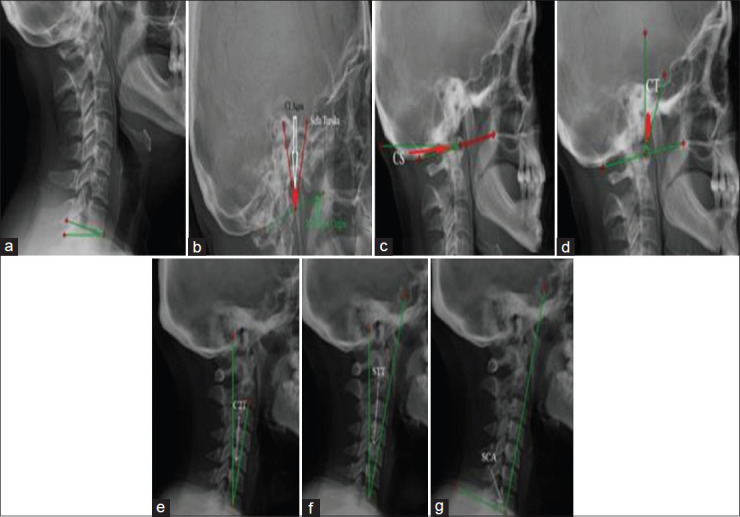

Materials and methods: This retrospective study included 102 CM patients and 71 healthy controls. Radiological measurements were obtained from cervical X-rays, with seven reference points used to calculate angles related to head positioning and cervical curvature. Angular parameters, including cranial incidence (CI), cranial slope (CS), cranial tilt (CT), C7 slope (C7S), and spinocranial angle (SCA), were analyzed to determine correlations with the COG of the head. Statistical analyses were performed using t-tests, ROC analysis, and Pearson/Spearman correlation tests.